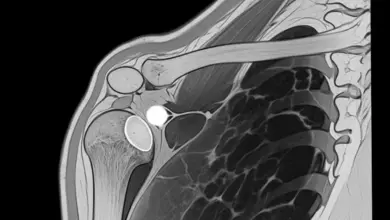

A clavícula é um osso em formato de “S”, que fica na parte superior do nosso tórax, sendo uma estrutura responsável por fazer a ligação entre o tronco.

Sendo assim, ela fica ligada a um osso que se chama “esterno”, e os braços,conectando-se assim ao ombro.

Portanto, não é exagero afirmar que a clavícula é um dos elementos mais importantes que permitem a mobilidade dos ossos superiores.

Mas, como é preciso saber qual porção foi lesionada, tamanho e gravidade da lesão, a radiografia é o exame mais comum.

Por meio dela, torna-se possível saber se houve ou não alguma fragmentação do osso.